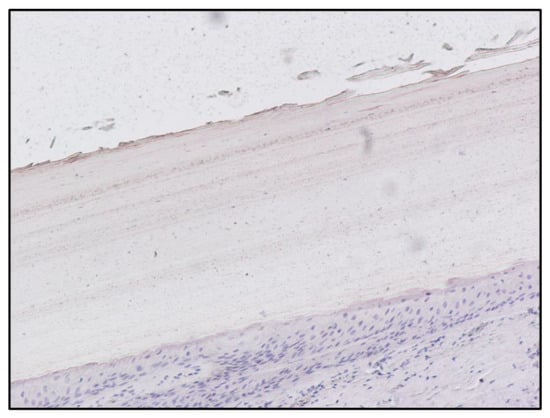

| Fingernail matrix | Area | Mean |

| Subject A (Figure 1) | 1,228,800 | 19.695 |

| Subject C (Figure 5) | 1,228,800 | 2.252 |

| Subject A matrix | Instrument | Morphine | 6-MAM | Codeine | Methadone | EDDP |

| Blood | GC-MS | 472 ng/ml | Negative | Positive | Positive | Positive |

| Scalp hair | UHPLC | 3.64 ng/mg | 1.42 ng/mg | Positive | Positive | Positive |

| Fingernail | UHPLC | 0.35 ng/mg | 0.43 ng/mg | Positive | Positive | Positive |